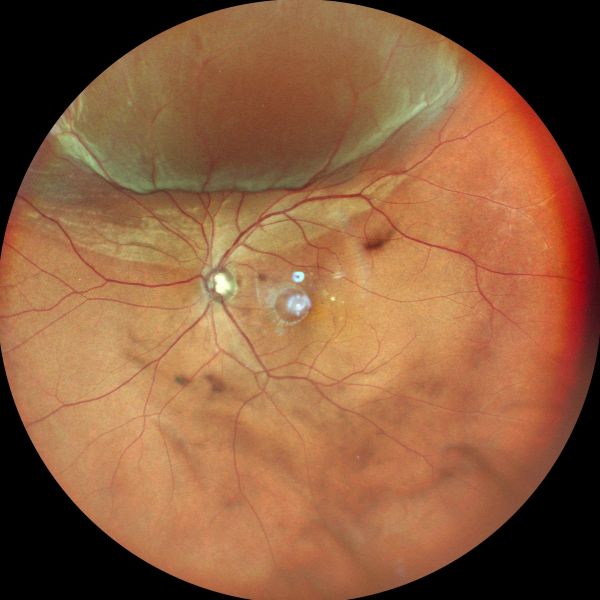

当院は「高度医療を身近に」を理念に、平成30年の開院以来、地域の皆さまに支えられながら診療を続けてまいりました。加齢黄斑変性や糖尿病網膜症などの網膜疾患、緑内障の専門的な診療に加え、小児の近視治療にも力を入れています。近視の進行が将来の視力障害につながる可能性があるため、早期の対策が重要と考えています。